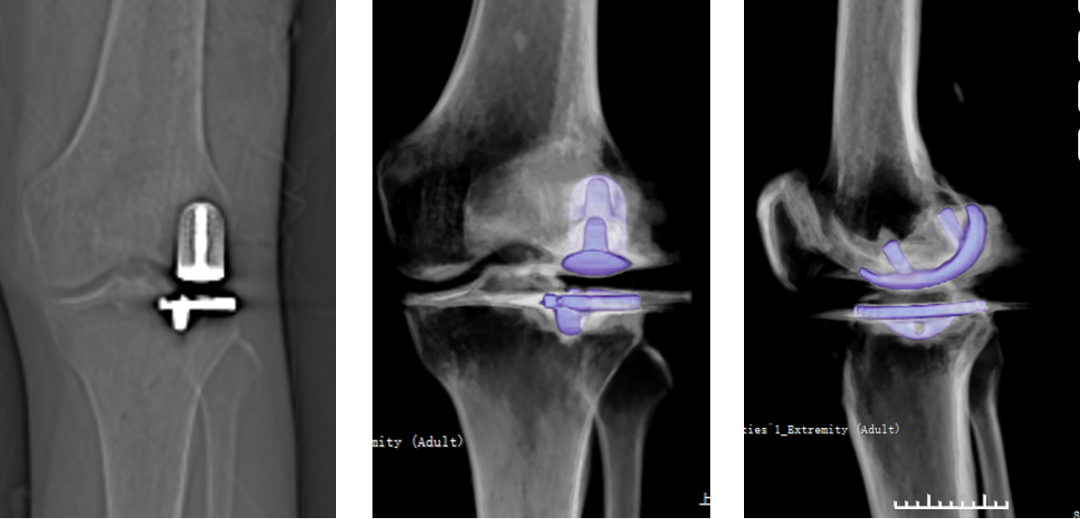

三、内侧LINK:registered: SLED假体位置

(全聚乙烯设计胫骨平台假体)

正位片标准胫骨和股骨假体位置

AP位假体位置:胫骨假体无内外翻,内侧缘超出胫骨平台内侧缘1mm; 股骨假体长轴与胫骨假体垂直,中线一致。

侧位片标准胫骨和股骨假体位置

侧位片假体位置:胫骨假体后倾3°,与胫骨平台前后缘齐平,股骨假体后倾40°,假体后缘与股骨后髁齐平。

胫骨假体厚度合适

胫骨垫片厚度合适:术前内翻畸形基本矫正,残留2-3°内翻。

股骨假体偏内放置,胫骨假体偏大

AP位胫骨与股骨假体位置:胫骨假体内侧悬挂>2mm,股骨假体中轴线与胫骨假体中线不一致,偏内侧。

股骨假体偏大且过度屈曲

侧位片假体位置:股骨假体后倾45°,假体后缘超出股骨后髁3mm, 胫骨假体后倾3°,与胫骨平台前后缘齐平。

四、外侧LINK:registered: SLED假体位置

AP位假体位置:胫骨假体外翻3°,内旋10°,外侧缘与胫骨平台外侧缘齐平; 股骨假体长轴与胫骨假体垂直,中线一致。

侧位片假体位置:胫骨假体后倾5°,与胫骨平台前后缘齐平,股骨假体后倾35°,假体后缘与股骨后髁齐平。

股骨假体偏内放置

AP位胫骨与股骨假体位置:股骨假体无内外内翻,中轴线与胫骨假体中线不一致,偏内侧。

侧位片股骨假体后倾不足

侧位片假体位置:胫骨假体后倾3°,完全覆盖胫骨平台前后缘,股骨假体后倾30°,股骨后髁覆盖不足。

胫骨假体偏厚

胫骨垫片厚度合适:术前外翻畸形矫正至轻度内翻。